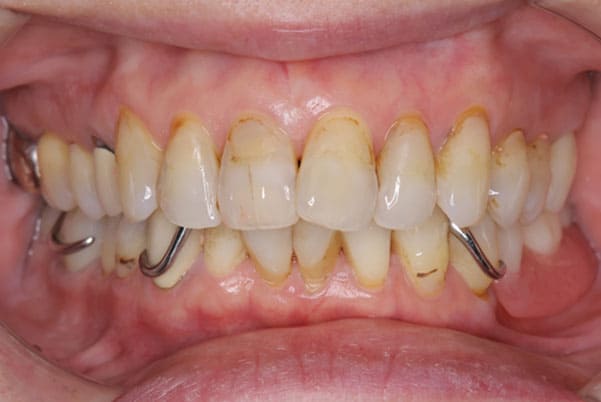

上の前歯が重度歯周病により動揺し、残せない状態のため、入れ歯も動揺がありました。

ご自身の歯に負担の少ないバネ、また見た目も改善

バネをかける歯は繋げることで強度を増し、歯への負担を軽減し、歯の寿命を長くする設計へ。

バネがかかる歯の被せ物は、歯への負担を減らし、入れ歯が動きにくいようになる形態をあらかじめ付与することで、より入れ歯の機能が高まります。

治療を行う際、被せ物や入れ歯は、別々に考えるのではなく、一口腔単位としてお口全体のことを考え最良の治療計画を立てることが歯の寿命、機能効果を向上させるため、専門医としてこのことは常に心掛けて治療を行っています。

治療前は上下奥歯の入れ歯が削れていることで、かみ合わせが低くなり唇もつむった状態でした。

かみ合わせを適切な高さに戻したことで、本来の自然な口元へ。